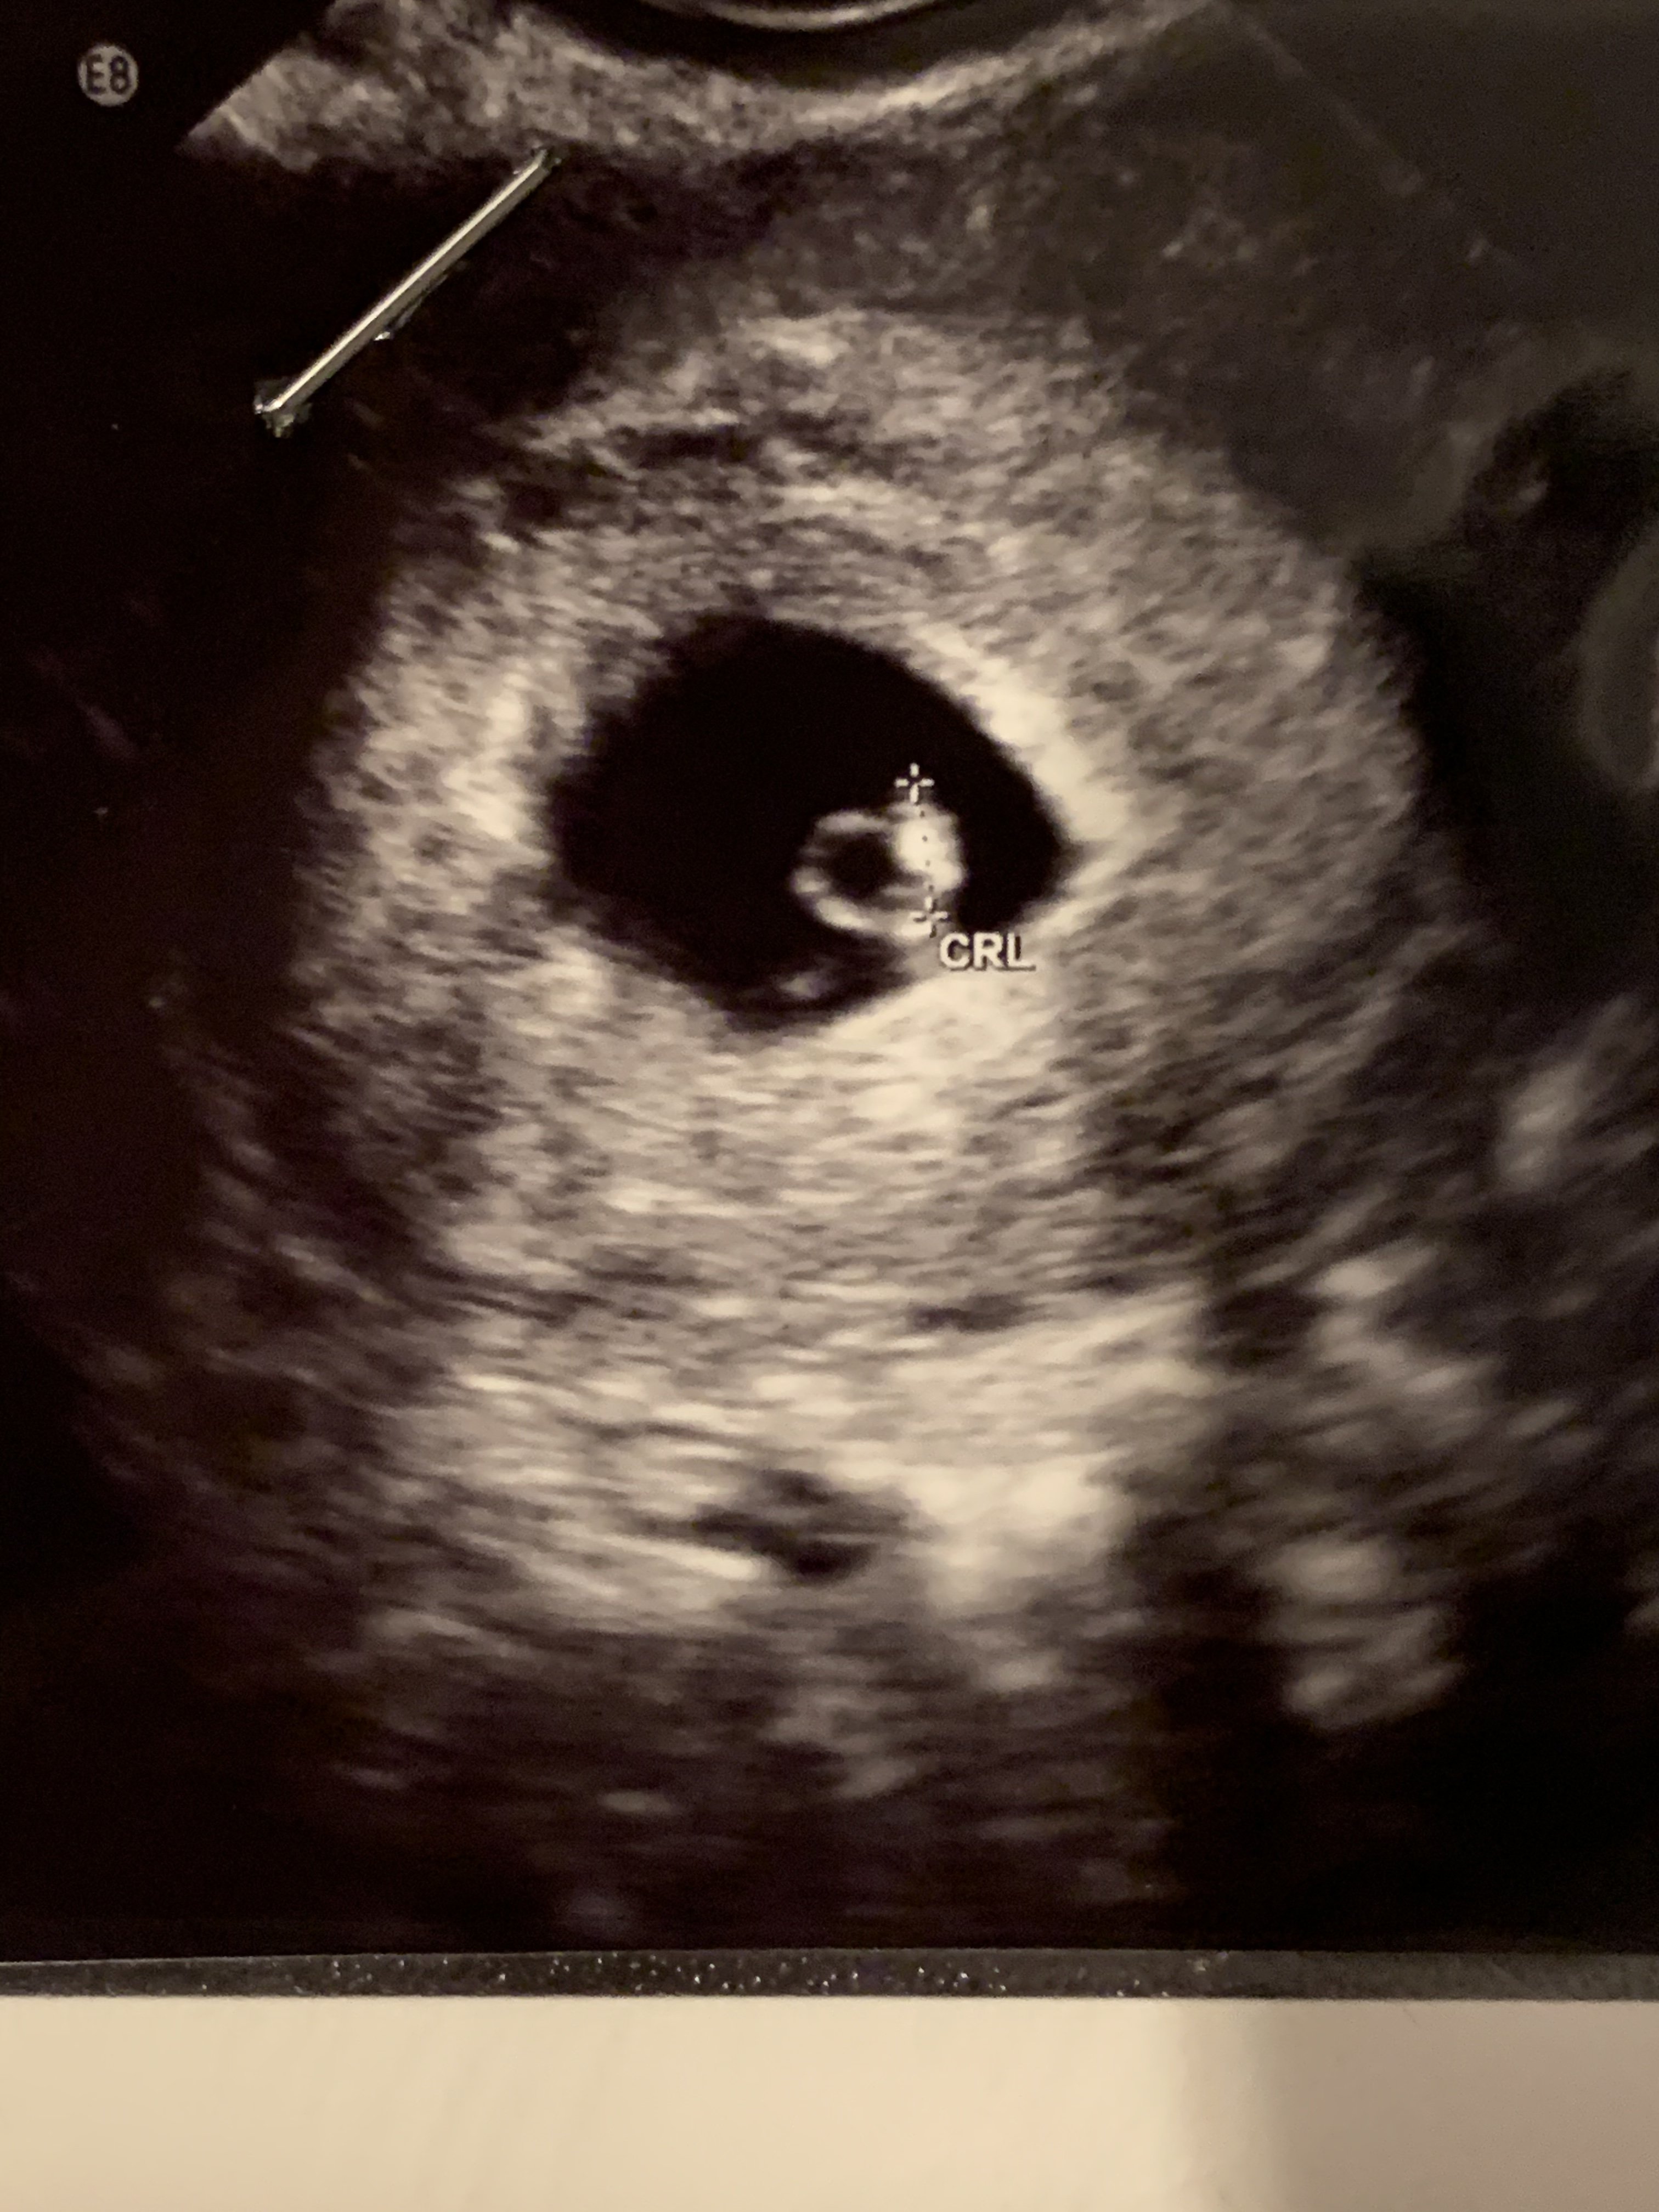

Dziewczyny! Jestem taka szczęśliwa. Byłam dzisiaj u ginekologa i wyszło, ze jestem w 6 tygodniu ciąży a dokładnie 6+1. Widać było zarodek i pani powiedziała, że widać też bijące serduszko ❤️. Na kolejna wizytę muszę zrobić oczywiście setki badań 😅

Załączniki

• B444C903-924F-452A-AB1C-BA7B8910C6AA.jpeg

B444C903-924F-452A-AB1C-BA7B8910C6AA.jpeg

1 MB · Wyświetleń: 135